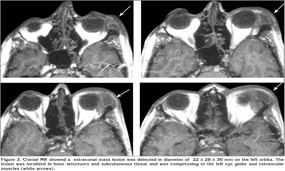

A 18-year-old Georgian male patient was admitted to the hospital with swelling above the eye, double vision, swelling and wound on the 3rd digit of the right hand. His physical examination revealed a palpable and readness mass lesion above the left eyelid (Figure 1). There was an edema, swelling and ulcerated wound on the soft tissue of the mid phalanx of the left third digit (Figure 2A). There were no relevant findings in the patient's history. A hand radiography showed the cystic appearance with expansion named "spino ventosa" in the bone tissue of the left third digit (Figure 2B). There were no abnormalities in his laboratory values. Sedimentation was 41 mm/hour. The patient underwent PPD test, which was positive. He was HIV-negative. Cranial MR was performed and a extraconal mass lesion was detected in diameter of 22 x 28 x 30 mm on the left orbita. The lesion was extending from the frontal to maxillary region (Figure 3). The lesion was localized in bone structures and subcutaneous tissue and was compressing to the left eye globe and extraocular muscles. CT of the thorax was taken, which showed fibrotic chronic infiltration and nodular lesions in the lung parenchyma and paravertebral hypodense lesions with loculi with a diameter of approximately 4 cm extending from the superior thoracic level downwards (Figure 4). Bronchoscopy revealed the edeumatous narrowing on the right upper bronchus. Acid-fast bacilli was negative by microscopic examination of bronchial lavage fluid. Excisional biopsy was performed from the mass on the patient's left eyelid and the histopathologic analysis showed "caseified granulomatous inflammation"(Figure 5). Based on the clinical, radiologic and pathologic findings, the patient was diagnosed with tuberculosis. The improvement was observed with antituberculosis treatment at lesions and symptoms of patient. The approval of patient and institution were taken to use their records for our study.

Signs and symptoms in patients with EPTB may vary by the involved organ. In our case, the cause for presenting to the hospital was a visual disorder. The presence of palpable mass over the eyelid, the MR obtained and it showed a mass lesion in diameter of 22 x 28 x 30 mm on the lateral portion of left orbital structures. It was localized in bone structures and subcutaneous fatty tissue. Also, it was compressing to the eye globe and extraocular muscles. The visual problem of patient was caused from the compress that this mass applied on the eye globe and extraocular muscles.